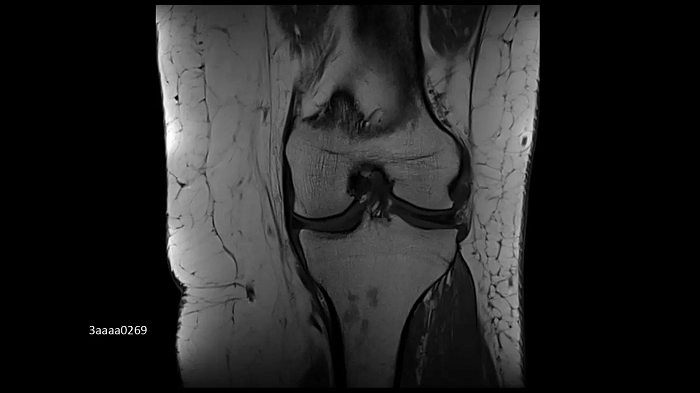

Knee imaging with the new Tx/Rx Knee 18

The new coil provides high-resolution knee imaging as well as a wider coil aperture to accommodate a larger patient population.

Image Credit: University Hospital Tübingen, Germany